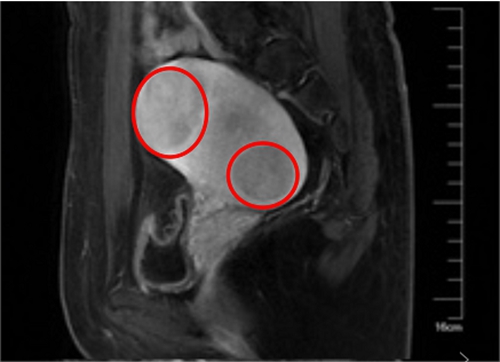

▲ 術(shù)前

入院后,醫(yī)院微無(wú)創(chuàng)中心團(tuán)隊(duì)成功利用聚焦超聲消融術(shù)為張女士消除肌瘤,術(shù)后4個(gè)小時(shí),張女士就已經(jīng)在病房里端起筆記本開(kāi)始工作了。術(shù)后第二天,張女士順利出院,并一再向醫(yī)護(hù)人員表示感謝:“沒(méi)想到竟然還有這種治療方式,不僅手術(shù)沒(méi)有創(chuàng)口,還可以提前計(jì)劃我的媽媽夢(mèng),真是太好了!”